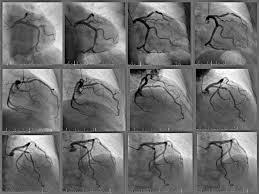

radiografia de contraste se inyecta una solucion de contraste, papilla de bario, se hace un placa y se ve el recorrido , se utiliza en infarto o angina de pecho angiografia coronaria

dilatacion de un vaso colocando un balon angioplastia coronaria